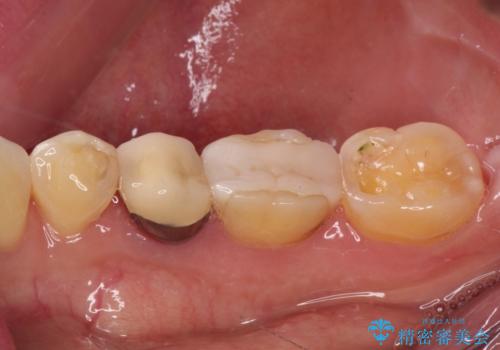

奥歯が欠けてしまった オールセラミッククラウンによる補綴治療

- 奥歯が欠けてしまった事を主訴として来院した患者様です。

頬側の欠けている範囲が大きく、以前治療した詰め物も大きいため、詰め物を外してむし歯を除去し、

形を整えて一度仮歯に置き換え、フルジルコニアクラウンにて補綴しました。

高強度のフルジルコニアクラウンは、強いかみ合わせでも壊れにくいです。

また審美的にも満足していただけました。